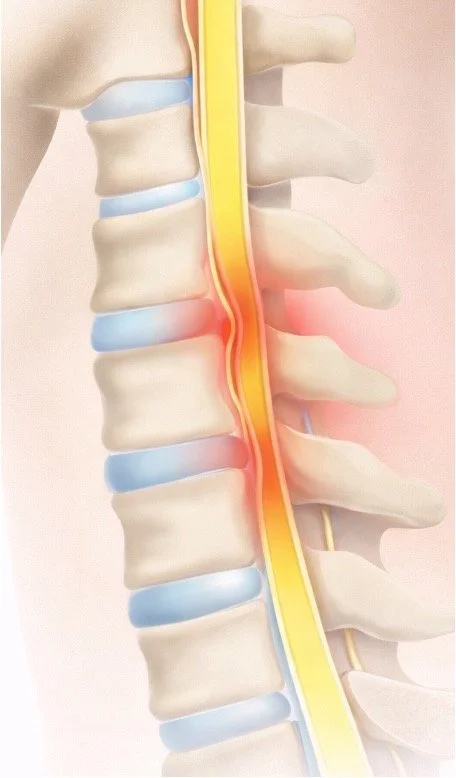

Medical illustration of a human spine showing a nerve pinch causing pain, with the affected area highlighted in red.

Cervical spinal stenosis means there is not enough space for the spinal cord or nerves in the neck.

The spinal canal normally protects the spinal cord. Over time, arthritis, disc bulging, or thickened ligaments can narrow this space and place pressure on the spinal cord or nerve roots.